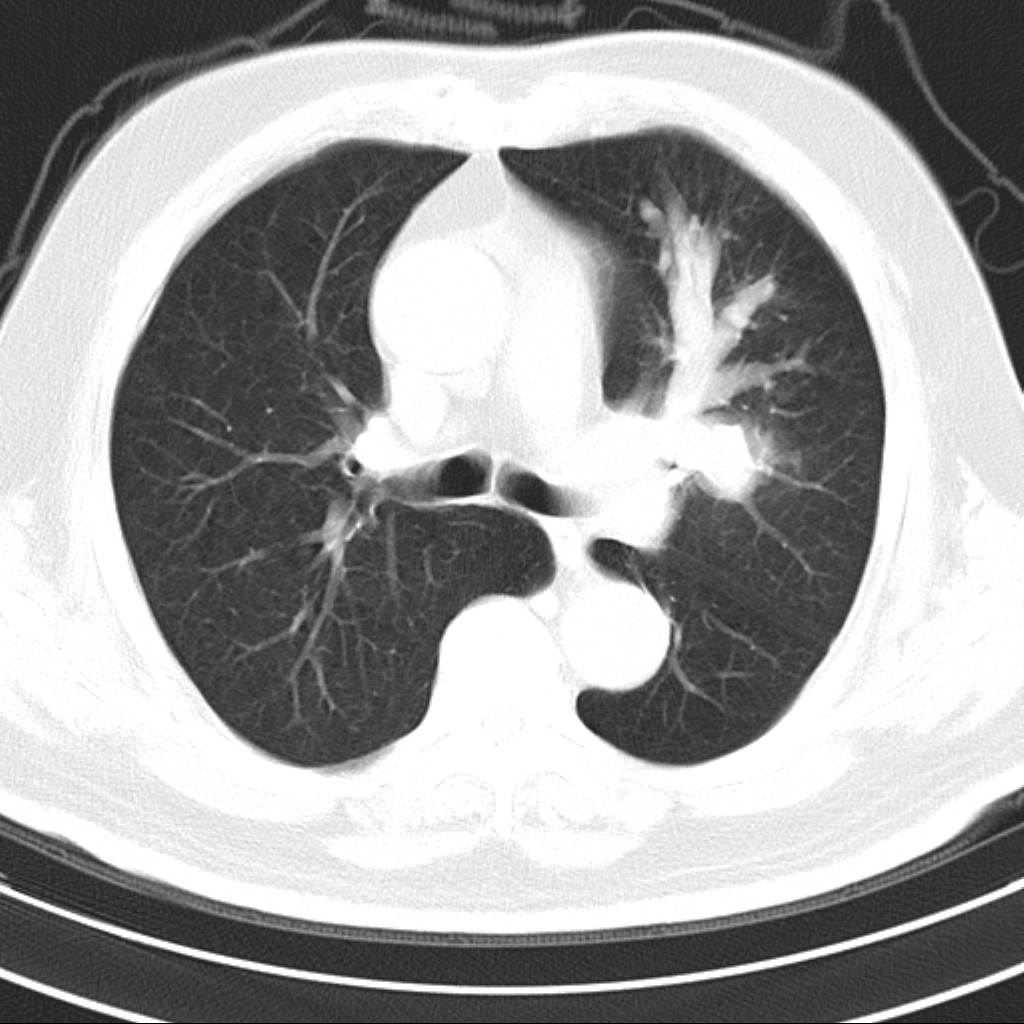

标题: CT18644:男,82岁,体检发现左肺阴影. [打印本页]

标题: CT18644:男,82岁,体检发现左肺阴影.

岁数太大,没有增强。麻烦见过的,给个诊断,顺便再说说病因

左侧中心型肺癌并粘液栓形成。很典型的。手套征。

支持 左肺上叶中央型肺癌并支气管内粘液栓形成。

支持考支气管扩张伴粘液栓,但导致粘粘液栓的病因有待进一步检查。支持左上叶支气管基部肿物,肺癌可能性大,但肿块似与肺动脉右支保持良好的伙伴关系,不除外为肺动脉扩张所致,建议增强。

左肺动静脉畸形,肺动静脉畸形(pavms)是肺血管发育异常,是肺动脉与肺静脉直接相通形成短路,通常包括一条供血动脉及一条或数条引流静脉,以及他们之间的异常血管团。约70%的患者伴发遗传性出血性毛细血管扩张症。 影像检查的目的在于确定病灶位置、大小、形态、数目。x线可表现为:1.结节型(直径小于3cm)2.团块型(直径大于3cm)3.弥漫型(肺内散在逗点状影),以团块状居多。 ct扫描可见单发或多发肺内结节,有的有蜿蜒迂曲的团块影,边缘光滑、锐利,增强ct扫描可见增粗、扭曲的血管影和/或类圆形的增粗的血管断面,甚至供血动脉及引流静脉。

平扫似avm,建议增强扫描。